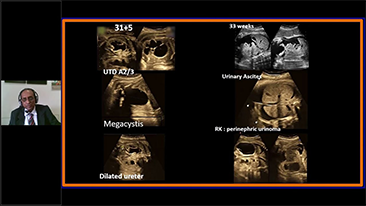

L'optimisation des flux de travail en gynÊcologie et obstÊtrique est indispensable pour traiter les volumes importants de patientes se prÊsentant pour des dÊpistages. Par exemple, les malformations du système nerveux central (SNC) font partie des anomalies congÊnitales les plus frÊquentes. Compte tenu des diffÊrentes conditions dans lesquelles sont rÊalisÊes les Êchographies, par exemple lorsque le f?tus est mal positionnÊ, il est particulièrement difficile de visualiser le plan transcÊrÊbelleux sur les Êchographies 2D. L'automatisation de la dÊtection et de la prise de mesures peut donc grandement amÊliorer l'efficacitÊ de l'imagerie.